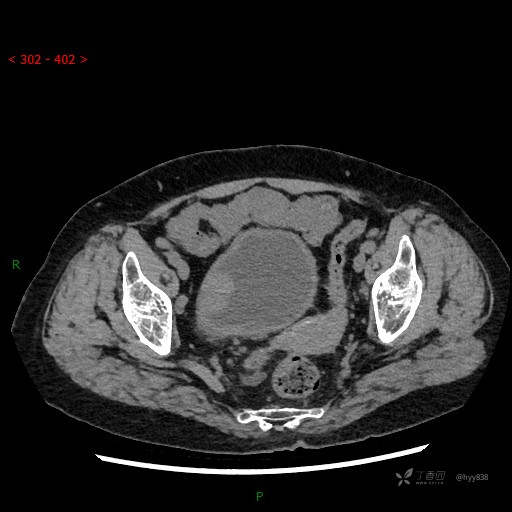

辅助检查:CT

膀胱CT平扫(2022.10.20)